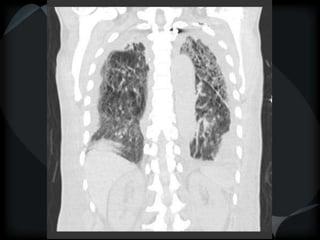

PHTN – PA 39mm

39.2mm

PHTN and septal thickening

? PVOD

PHTN – PA39mm 39.2mm

PHTN and septalthickening ? PVOD